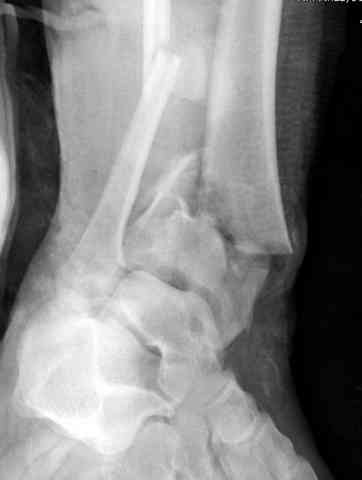

Дополнительные ренгенограммы после дистракции и

обязательная комьютерная томография дают возможности разузнать топографию расположения фрагментов, что немаловажно для планирования хирургического доступа.

По апексу фрагмента ориентируется при планировании

фиксации, также предоперационно определяется

направление фиксирующего материала: шурупа или спицы с упорной площадкой.

Первичная пластина или интрамедуллярный фиксатор на малоберцовую зависит от характера перелома, косые и многооскольчатые пластинами, а поперечных можно интрамедуллярными фиксаторами. Восстановленная длина малоберцовой служит ориентиром и помогает определению высоты большеберцовой во время восстановления.

Переломы пилона сопровождаются ударом со сминанием в метафизарной части большеберцовой, то есть со значительной потерей костного объема.

При репозиции суставных поверхностей образуются полости в метафизарных отделах, без заполнения их

структуральными элементами невозможно предохраниться от посттравматической деформации. Латеральная колонна удерживается малоберцовой поэтому голень деформируется в варус.